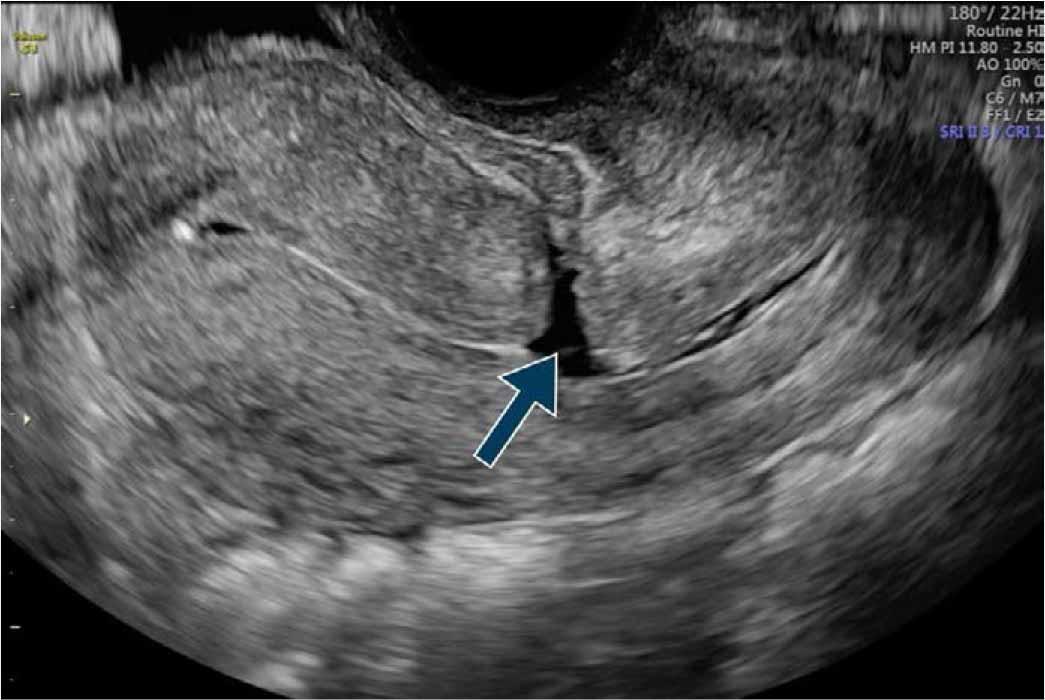

A uterine isthmocele in the sagittal plane by TVUS [27].